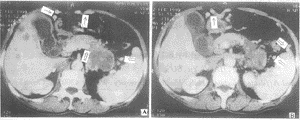

图1 CT显示胰体尾巨大囊肿压迫阻塞脾静脉伴胃短静脉(开尾前)、胃网膜静脉(黑箭头)曲张,均为手术证实。胃短静脉从脾门发出,行于脾胃韧带内;胃网膜静脉沿胃大弯走行

图2 胰体尾癌伴脾静脉中断(空心箭),同时显示胃短静脉,胃网膜静脉曲张

图3 A.显示食管下段静脉曲张;B.显示胃冠状静脉曲张

19例孤立性脾静脉阻塞中,只有1例脾动、静脉同时阻塞者未出现胃周静脉曲张,其余18例均出现了胃周静脉曲张,因此该18例诊断胰源性区域性门静脉高压(pancreatic segmental portal hypertension,PSPH)成立。18例PSPH中(见表1)EV曲张2例(11%),表现为食管下端黏膜下血管增多;GCV曲张13例(72%),其中曲张明显(GCV主干直径≥5mm)5例,不明显者8例,后者表现为GCV迂曲延长或血管断面增多,但GCV主干直径<5mm;GSV曲张(见图1、2)17例(94%),曲张明显者14(其主干直径≥4mm),不明显者3例;GEV曲张17例(94%),其主干直径均≥5mm。30例门静脉高压(portal hypertension,PH)中(见表1),EV曲张(见图3A)30例(100%),其中曲张明显26例,表现为食管下端静脉蚯蚓状或瘤样扩张;GCV曲张(见图3B)30例(100%),其中曲张明显者27例;GSV曲张8例,曲张明显者5例;GEV曲张6例。同时,29例出现了脾静脉的迂曲、扩张(直径≥1cm)。